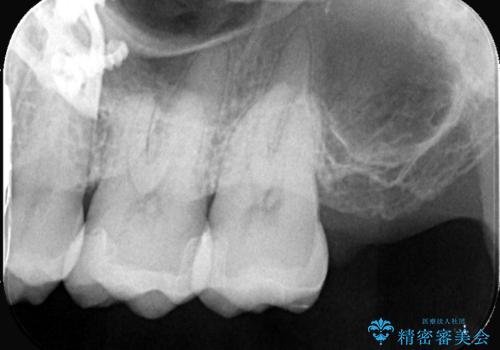

初診でいらした患者様で、口腔内を確認したところ左上6番目と7番目の歯の接する面を中心に両方の歯に虫歯が認められたため、セラミックインレーでの修復治療となりました。

左上6番の歯には元々修復物が入っていましたが、それも一度除去し新たにMOD窩洞のセラミックインレーをセットしました。

左上7番咬合面裂溝の着色部分は今後エアフロー等を使用し落としていく予定です。